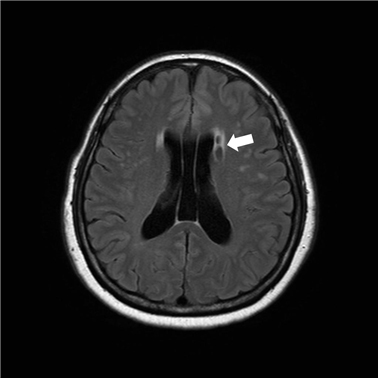

뇌혈관이 막히거나 터지는 질환을 부르는게 뇌졸중이고 그 중 뇌혈관이 막히는게 뇌경색 그리고 뇌혈관이 터지는 것을 뇌출혈이라고 합니다. 뇌졸중은 영구적인 손상이 많다고 하며 증상에 따라 전신이나 육체 일부 기능이 마비되는 등의 극심한 후유증이 남는 무서운 질병입니다 오늘은 뇌경색 초기증상에 대하여 알려드리도록 하겠습니다.

허혈성 뇌졸중은 발생 기전에 따라 대혈관 질환에 의한 뇌경색, 심인성 뇌경색 또는 심인성 뇌경색, 소혈관 질환 또는 틈새 뇌경색, 기타 드문 이유가 되는 것에 의한 뇌경색으로 나누어져요. 에피소드는 일정 기간 동안 증상이 완전히 가라앉는 경우입니다.

허혈성 뇌졸중의 대표적인 이유가 되는 것은 고혈압, 당뇨병, 고지혈증 등으로 인해서 뇌에 혈액을 전달하는 혈관에 동맥경화(동맥경화)가 발생하여 뇌로 가는 혈류를 차단하는 것입니다.